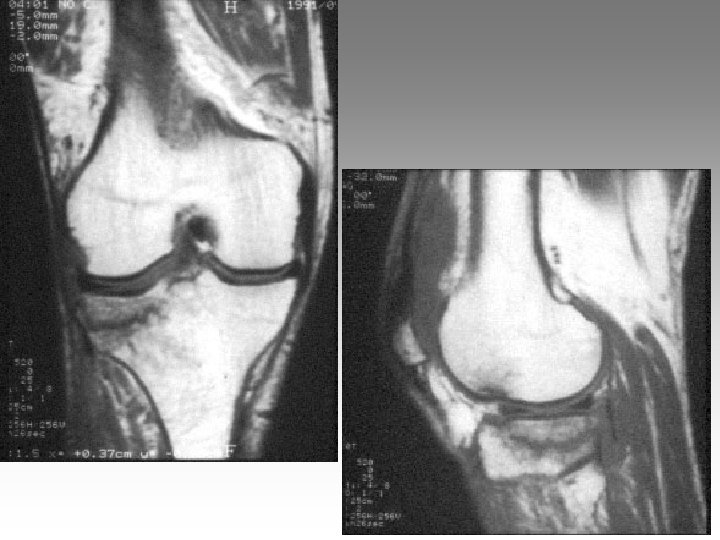

Hanche, T. , fract. fatigue Tendinites bursites, radic. Genou douloureux non traumatique Sémiologie Ponction +++ mécanique inflammatoire Rx inflammation Rx N Rx a. N < 40 ans interligne pincé Arthrose FT - FP contexte +++ > 40 ans Biologie, BS, Rx, IRM, écho interligne normal IRM AND, FF Paget, HOV ONA, OAN OAPH Ostéochond. infection IRM Arthroscopie Scinti. Os. LC Ménisque Coagul. PR, RP, Still, LED, SA…. Goutte, CCA AND ONA Ostéochondrite Pyogène, BK, Gono. , autres Hydarthrose X? Ostéochondromatose Synonite VN, T. , coag.

Genou douloureux non traumatique Sémiologie Ponction +++ mécanique inflammatoire Rx inflammation Rx N Rx a. N < 40 ans interligne pincé Arthrose FT - FP contexte +++ > 40 ans Biologie, BS, Rx, IRM, écho interligne normal IRM AND, FF Paget, HOV ONA, OAN OAPH Ostéochond. infection IRM Arthroscopie Scinti. Os. LC Ménisque Coagul. PR, RP, Still, LED, SA…. Goutte, CCA AND ONA Ostéochondrite Pyogène, BK, Gono. , autres Hydarthrose X? Ostéochondromatose Synonite VN, T. , coag.

Genou douloureux non traumatique Sémiologie Ponction +++ mécanique inflammatoire Rx inflammation Rx N Rx a. N < 40 ans interligne pincé Arthrose FT - FP contexte +++ > 40 ans interligne normal IRM AND, FF Paget, HOV ONA, OAN OAPH infection Biologie, BS, Rx, IRM, écho IRM Arthroscopie Scinti. Os. LC Ménisque Coagul. PR, RP, Still, LED, SA…. Goutte, CCA AND ONA Banal, BK, Gono. , autres Hydarthrose X? Ostéochondromatose Synonite VN, T. osseuse